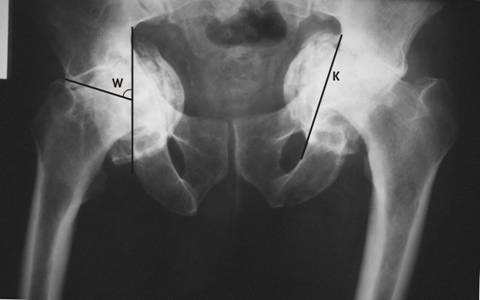

Examenul radiologic efectuat pe radiografia de fata a bazinului (fig. 1) releva prezenta semnelor radiologice de protruzie acetabulara. Unghiul Wiberg de acoperire a capului femural (W) a avut valori de 73 pe dreapta si 84 pe stanga. Acest unghi este format intre 2 linii: o verticala prin centrul capului femural si o linie ce uneste centrul capului de spranceana cotilului si are valor normale de 25-40. Marginea interna a acetabulului este situata intern de linia ilio-ischiatica a lui Kohler, la distanta de 14 mm pe dreapta si 18 mm pe stanga (pe radiografia de fata a unui pelvis normal, marginea interna a acetabulului este situata extern de linia lui Kohler). Masurand distanta de la marginea superioara a ramului ascendent al pubisului la conturul protiunii protruzionate a acetabulului, am obtinut valorile de 11 mm pe dreapta si 15 mm pe stanga. Astfel, am incadrat leziunea pe partea dreapta ca fiind de grad II sau moderata (6-15 mm), iar pe partea stanga, de grad III sau severa (peste 15 mm).

De asemeni, se observa pensarea spatiului articular bilateral, prezenta osteofitelor si modificarile de structura ale capului femural bilateral, fapt ce denota aparitia de modificari degenerative (coxartroza bilaterala).

Fig. 1. Radiografia de fata a bazinului. Pe soldul drept este figurat

unghiul Wiberg (W), iar pe cel stang linia ilio-ischiatica Kohler (K).